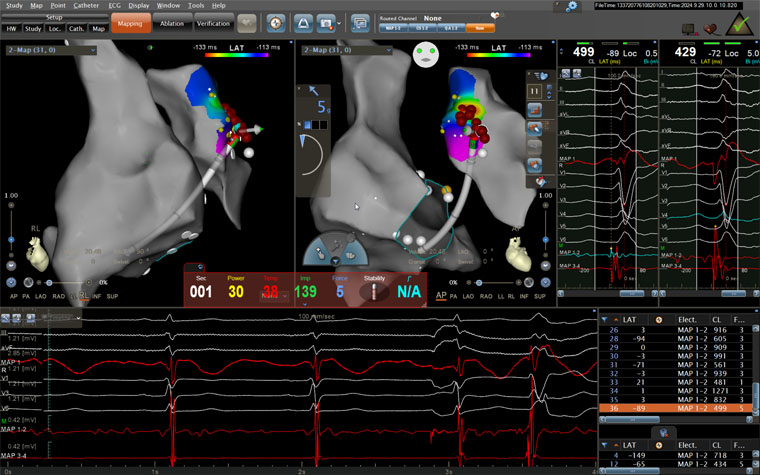

術中患者射頻消融情況

手術當日,醫護人員連接多導電生理儀和CARTO三維標測系統,對病人進行術前消毒,局麻后穿刺股靜脈,操作ST消融導管至右房,建立右心三維解剖。術中,姚鐵柱副主任操作ST消融導管經三尖瓣進入右室流出道,于右室流出道后游離壁標測到最早激動靶點,誘發室早形態與原體表心電圖室早形態相同,給予放電消融,患者室早消失;繼續行冠脈造影術,導管造影結果顯示,前降支中段可見約50%局限性狹窄。術畢,患者安返病房,心電圖示為“竇律規整”;繼續給予心電監測,患者無室早出現,心慌、氣短癥狀消失。根據冠狀動脈造影結果對其調節藥物治療,患者胸痛、背痛癥狀得到緩解。術后僅不到兩日,患者便順利出院。